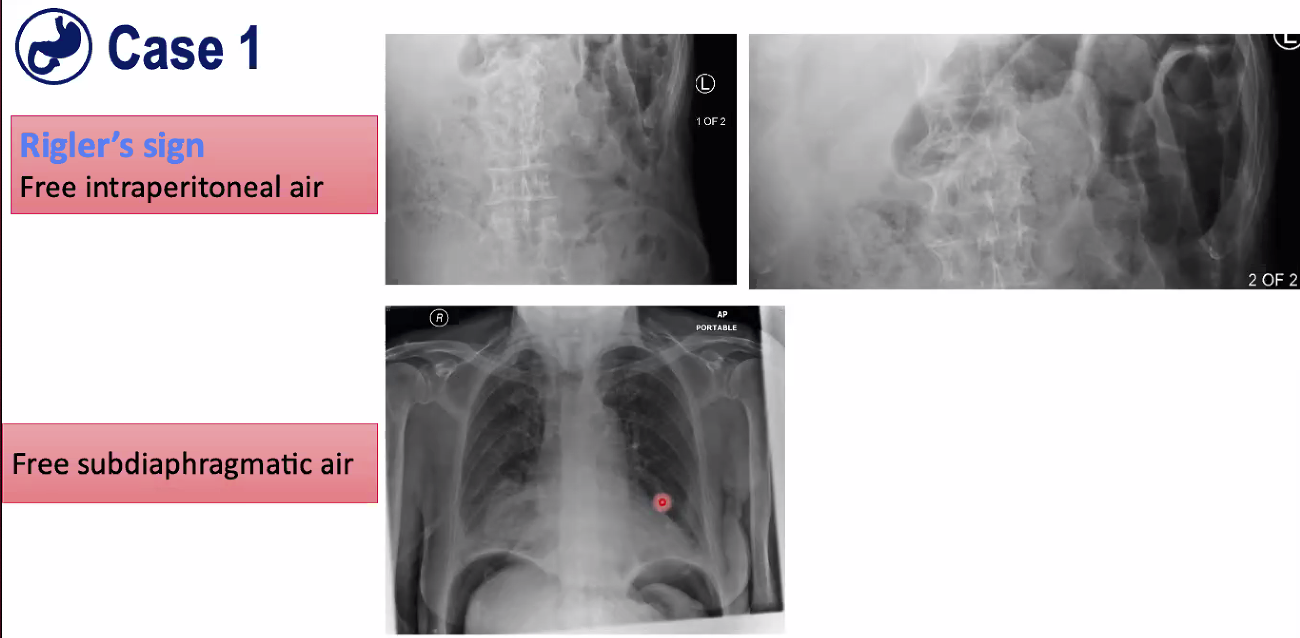

Bottom-shows erect chest X-ray, remember air goes upwards. Can see a lot of air under diaphragm (sub-diaphragmatic air), big gap between right diaphragm and liver, which is normally snuggly adjacent to the liver.

This is why we did an erect chest x-ray.

Abdomenal X-ray: On top left image, on left you can see faeces in large bowel, and on top right of image everything seems to be a lot clearer. Looking at image on right we can see small bowel and we can see both sides of the wall very clearly. This means there is air on the inside and air on the outside, and that’s known as Rigler’s sign which is free intraperitoneal air. It’s quite subtle but it’s an important sign to remember and that’s exactly why you’re doing plain abdominal X-rays.

The Rigler sign, also known as the double-wall sign, is a sign of pneumoperitoneum seen on an abdominal radiograph when gas is outlining both sides of the bowel wall, i.e. gas within the bowel’s lumen and gas within the peritoneal cavity.